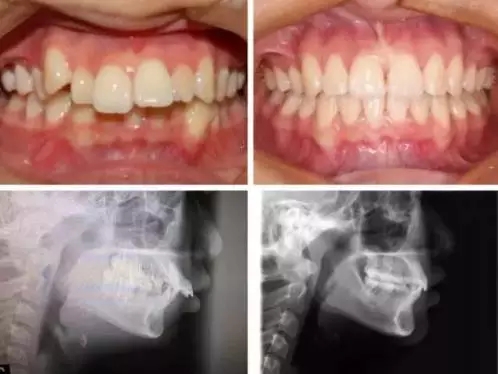

牙齿矫正的一切前提都是建立在不损害牙齿健康上的,所以我们施加在牙齿上的力度在牙齿可接受的生理移动范围之内。根据科学的研究,牙齿每一个月移动一毫米,就已经是非常非常快的了,如果再快的话,可能会引起:

1,牙根的吸收,就是让牙根变短。

2,牙槽骨的吸收,就是让牙根周围的骨头高度降低,自然这种牙齿移动就不是健康的了。

当然,每个个体的生理情况不一样,牙齿的移动速度不同,矫正时间也会不同,另外有一种情况必要要了解,骨性的矫正,尤其是骨性龅牙,因为牙槽骨非常致密,改建过程较困难,所以矫正时间相对要增加,通常会超过2年甚至更长。